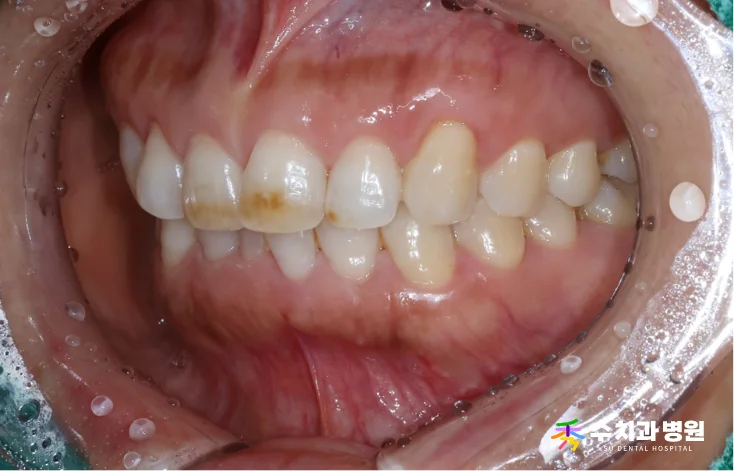

[📸 치료 전 사진] (촬영일: 2025년 8월)

10년 전부터 앞니 변색이 진행된 상태였고,

미소를 지을 때마다 신경이 쓰인다고 하셨습니다.

검진 결과 위 앞니 일부가 어둡게 변해 있었습니다.

특히 왼쪽 위 첫 번째 앞니는 약간 틀어져 있었습니다.